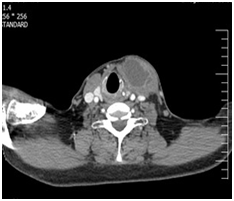

A 56-year-old male, smoker, with no significant past medical history, presented with a 18-weeks history of a nodular swelling of the neck. The patient also reported dry cough without fever for the past year. There was no history of weight loss, anorexia or asthenia. Physical examination revealed a 6cm cystic nodular mass in the left - anterior neck which seemed to be in the left lobe of thyroid gland. The throat was normal. Body temperature was 37°C, the heart rate was 92/min, and blood pressure was 149/80mm Hg. Enlarged lymph nodes were not palpable in rest of body. Chest- X-ray examination was normal. Thyroid function tests were in the normal range. WBC: 7000/mm3 with a normal differential count, haematocrit: 38%, haemoglobin: 12.7g/dl, platelets: 424.000/mm3. Erythrocyte sedimentation rate was 12mm in the first hour and the C reactive protein (CRP) was 3.4mg/l (normal value <5mg/l). The liver functions tests were normal. Ultrasonography and CT-scan of the neck revealed that the left lobe of the thyroid gland contained many thick fluid material with cystic changes resulting in an enlargement of the left lobe gland (Figure 1). The rest of the gland had a normal echogenicity and regular margins. The chest X-ray was normal. Tuberculin test was negative. ultrasound guided fine-needle aspiration was performed, AFB in aspirated pus by Ziehl Nelsen stain was negative. The specimen submitted for culture, bacterial and tuberculosis was negative too. Sulfure- granule for actinomycosis was negative. The patient had surgery, which yellow pus aspirated (Figure 2). Resection of the left lobe and istem was performed, the rest of the gland showing no abnormality. On gross examination, the specimen was necrotic and debris tissue (Figure 3). Microscopic examination revealed necrotizing epithelioid granulomas with Langhans’ giant cells (Figure 4). The diagnosis of thyroid tuberculosis was therefore made. Acid fast bacilli (AFB) were absent in the sputum. Abdominal ultrasonography revealed no lymph node enlargement. The patient was placed on isoniazid (300mg per day), rifampicin (600mg per day), ethambutol (1200mg per day) and pyrazinamid (1500mg per day) for 2months and isoniazid and rifampicin for the subsequent 4months. The clinical outcome was good. Ultrasonography of the neck and of the abdomen at 8months of antituberculous treatment revealed no abnormality of the thyroid gland. The enlarged lymph nodes of the jugular and carotid chains were not present.Thyroid functions test (T4, T3 and TSH) was normal.

Figure 1 CT-scan of neck show a cystic lesion in thyroid.